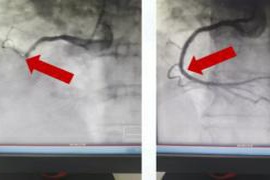

转入后,医院急救绿色通道同步启动,患者直接被推送至导管室行急诊PCI(经皮冠状动脉介入治疗)。术中患者突发血压、心率持续下降,陷入循环衰竭状态。麻醉与介入团队立即联合抢救:静脉输注多巴胺、去甲肾上腺素维持血压,注射阿托品提升心率,同时快速推进冠脉造影。影像显示患者右冠状动脉自开口完全闭塞,导丝团队精准操作通过闭塞段,于右冠开口植入1枚支架。虽血管近端血流恢复,但远端可见大量血栓影,团队随即实施导管血栓抽吸,并冠脉内注射替罗非班抗栓治疗。